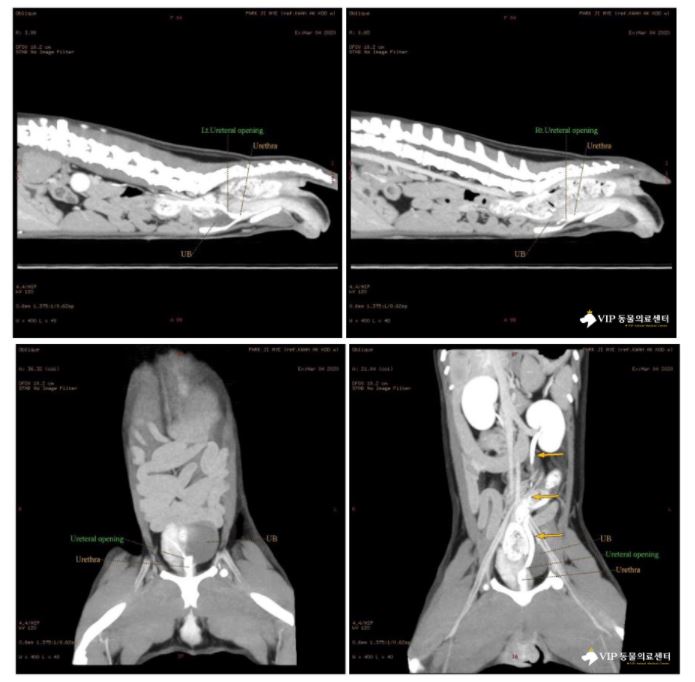

5) CT 검사

양측 요관의 방광 정상 개구부가 관찰되지 않으며, 조영을 실시하였을 때 비정상적으로 근위 요도에서 조영제가 관찰되었습니다.

또한 신장에서 조영제가 배출된 후 요관 근위요도 방광 순으로 조영제가 이동하는 것이 관찰되었습니다.

(정상적 조영제 이동 : 요관 방광) 따라서 요코는 방광-요도 연결부 위치로 요관이 개구할 가능성이 높게 판단되었습니다.